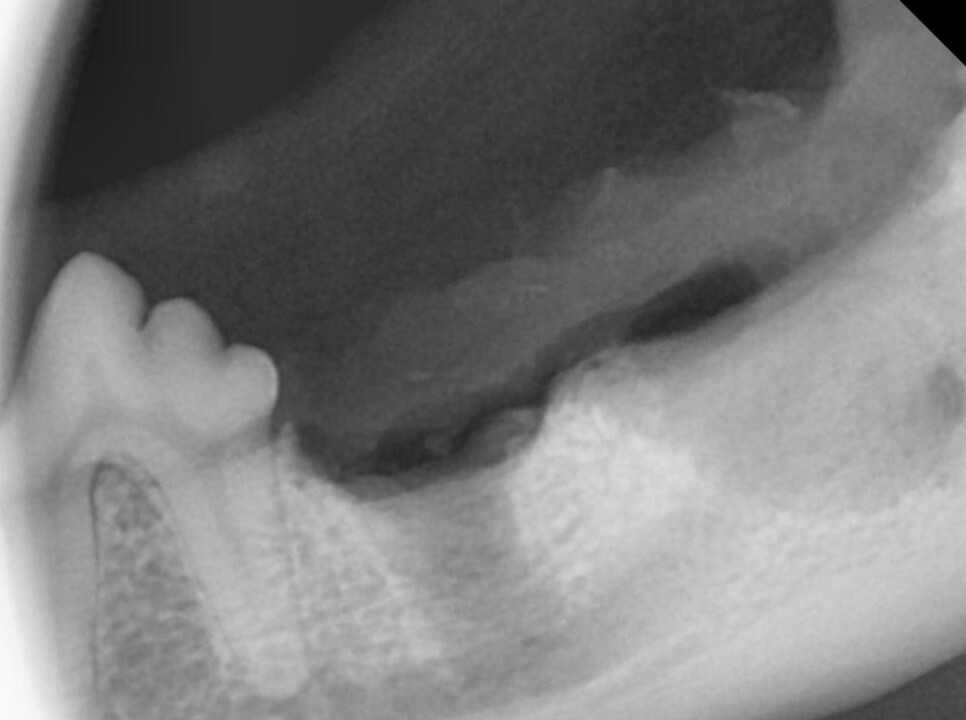

사진을 보면 치아 아래쪽 잇몸에 혹 비슷한 것이

관찰되고 있습니다.

방사선 검사상 같은 부위에 치주염이 있는 것을

확인할 수 있었습니다. 또한 바로 뒤의 두 번째 어금니에도 병변이 확인되었습니다.